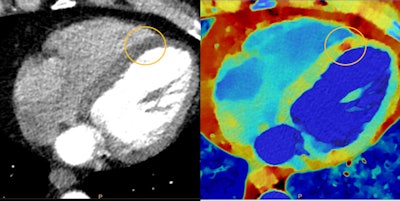

Myocardial perfusion defects are difficult to visualize on conventional CT due to beam-hardening artifacts. Spectral CT results reduce beam-hardening artifacts, enabling easier visualization and quantification of perfusion defect. Image courtesy of Philips.

Myocardial perfusion defects are difficult to visualize on conventional CT due to beam-hardening artifacts. Spectral CT results reduce beam-hardening artifacts, enabling easier visualization and quantification of perfusion defect. Image courtesy of Philips.Philips also made workflow a major priority in designing Spectral CT 7500. Spectral scanning can now be expanded to all types of scanning conditions, ranging from pediatric patients to bariatric cases. The company has reduced by 68% the number of mouse clicks required to produce a spectral scan, Boussebaa said.